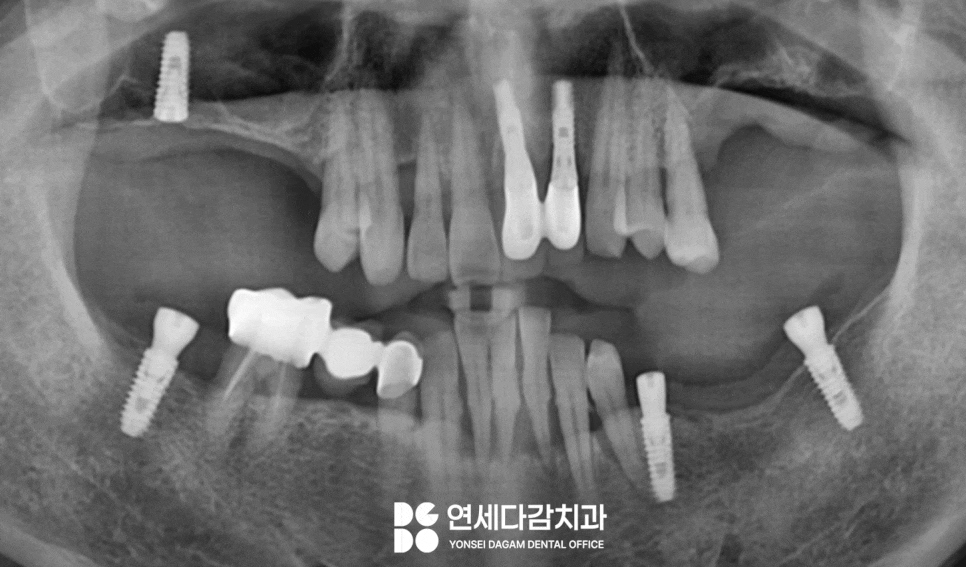

가락동 치과 에서 예를 들자면

앞니가 많이 흔들리고

뼈 상태가 좋지 않거나,

위턱뼈가 얇아져 별도의 뼈이식술 같은

시술 동반이 필요한 경우가 있습니다.

특히 위턱 어금니 부위는

골밀도가 낮고

저작 시 힘이 많이 받는

부위이기 때문에 임플란트 실패율이

높게 나타나는 곳입니다.

골 높이가 낮은 경우에는 상악동이라는

점막에 손상을 줄 수 있기 때문에,

점막을 위로 거상하여

공간을 확보하고 골이식을 시행한 뒤

고정체를 식립하는 단계적 접근이 필요합니다.

그러나 이처럼 뼈 높이가 낮거나

골질이 좋지 않은 경우에는

골 유착 과정이 더 오래 걸릴 수 있습니다.

따라서 뼈의 재생을

촉진할 수 있는 성분이 처리된

것을 선택하는 것이 중요한 것이죠.

아래 앞니 부위 역시

뼈 상태가 좋지 않아

안정적으로 결합할 수 있는

타입을 선택하여

고정력을 확보합니다.

이 과정을 통해 수술 부위 모두

골 유착이 원활하게 진행되어

안정적인 결과를 얻을 수 있게 됩니다.